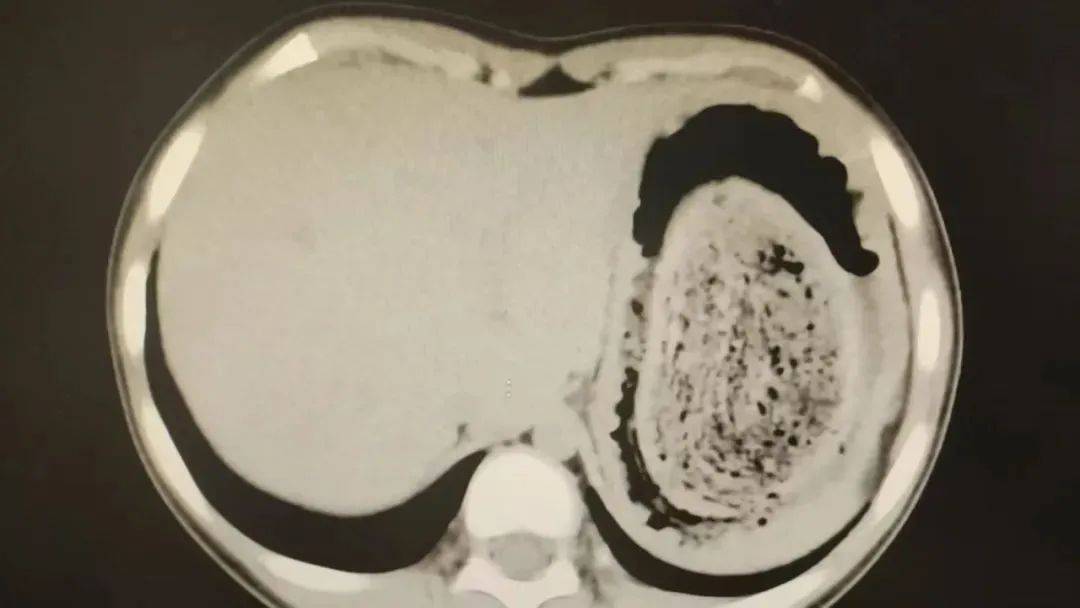

在胃镜帮助下,妮妮胃里的情况逐渐明了皇冠信用网登2。一个滚圆黑色的毛发球混合着食物残渣占据整个胃腔,这些头发相互缠绕形成一个实心的“发石”,此外胃里还有一个鸡蛋大小的溃疡。

10岁女孩园园(化名)因持续3天的上腹痛伴呕吐被紧急送医皇冠信用网登2。影像学检查结果显示,她的胃部存在一个巨大的团块状阴影,初步怀疑为异物堵塞。据家长回忆,园园从1年前开始就有偷偷吃头发的习惯,但家人并未重视,直到这次症状严重才意识到问题的严重性。